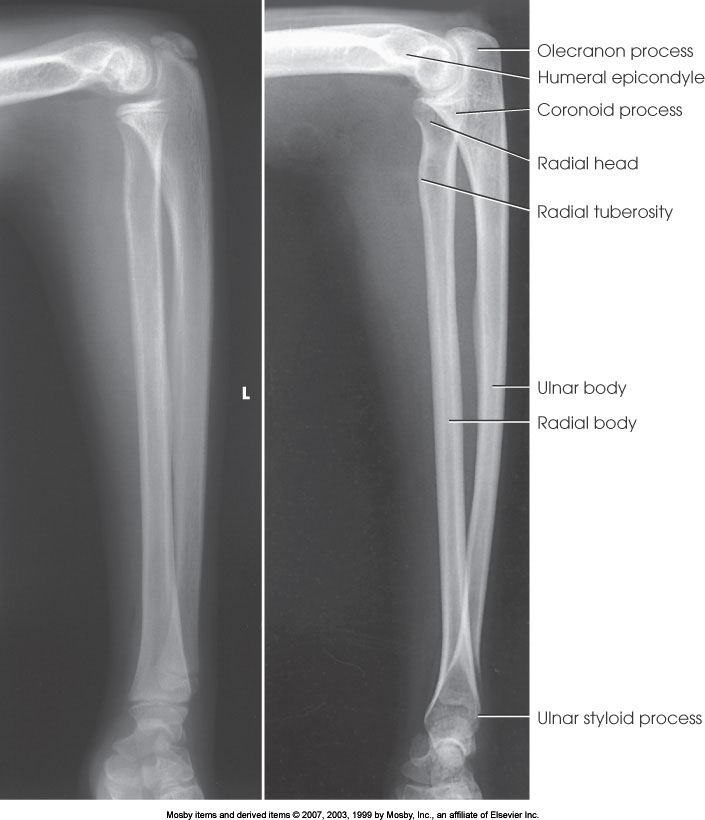

AP Forearm

What position is demonstrated?

Lateral Forearm